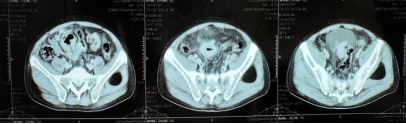

影像学检查:2024年7月30日,院外腹部CT显示乙状结肠管壁增厚,考虑肿瘤性病变(cT3N2,图1),2024年8月5日,肝脏MRI显示肝脏多发转移灶(侵犯门静脉右支、肝右静脉,图2)。2024年8月2日胸部CT显示双肺结节待排(图3)。

图1. 腹部CT